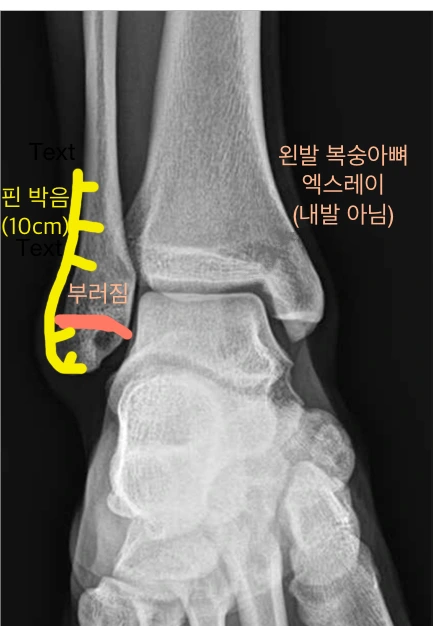

위 그림처럼

복숭아뼈 하단 1cm 정도를 남겨두고 부러진 거야(골절)

그런데 그 아랫 부분이 인대랑 잘 붙어 있어서 잘 움직인다데

그래서 잘 안 붇기 때문에 핀을 박아야 한대. 플레이크 후크(?) 정확한 명칭이 기억 안 나네

아무튼 저 1cm 부러진 것 때문에 10cm 자리 후크를 뼈에 박아야 하고

그 10cm 후크를 박기 위해서 12cm 절개를 하고 핀을 박는 수술을 해야 한다는 거지.